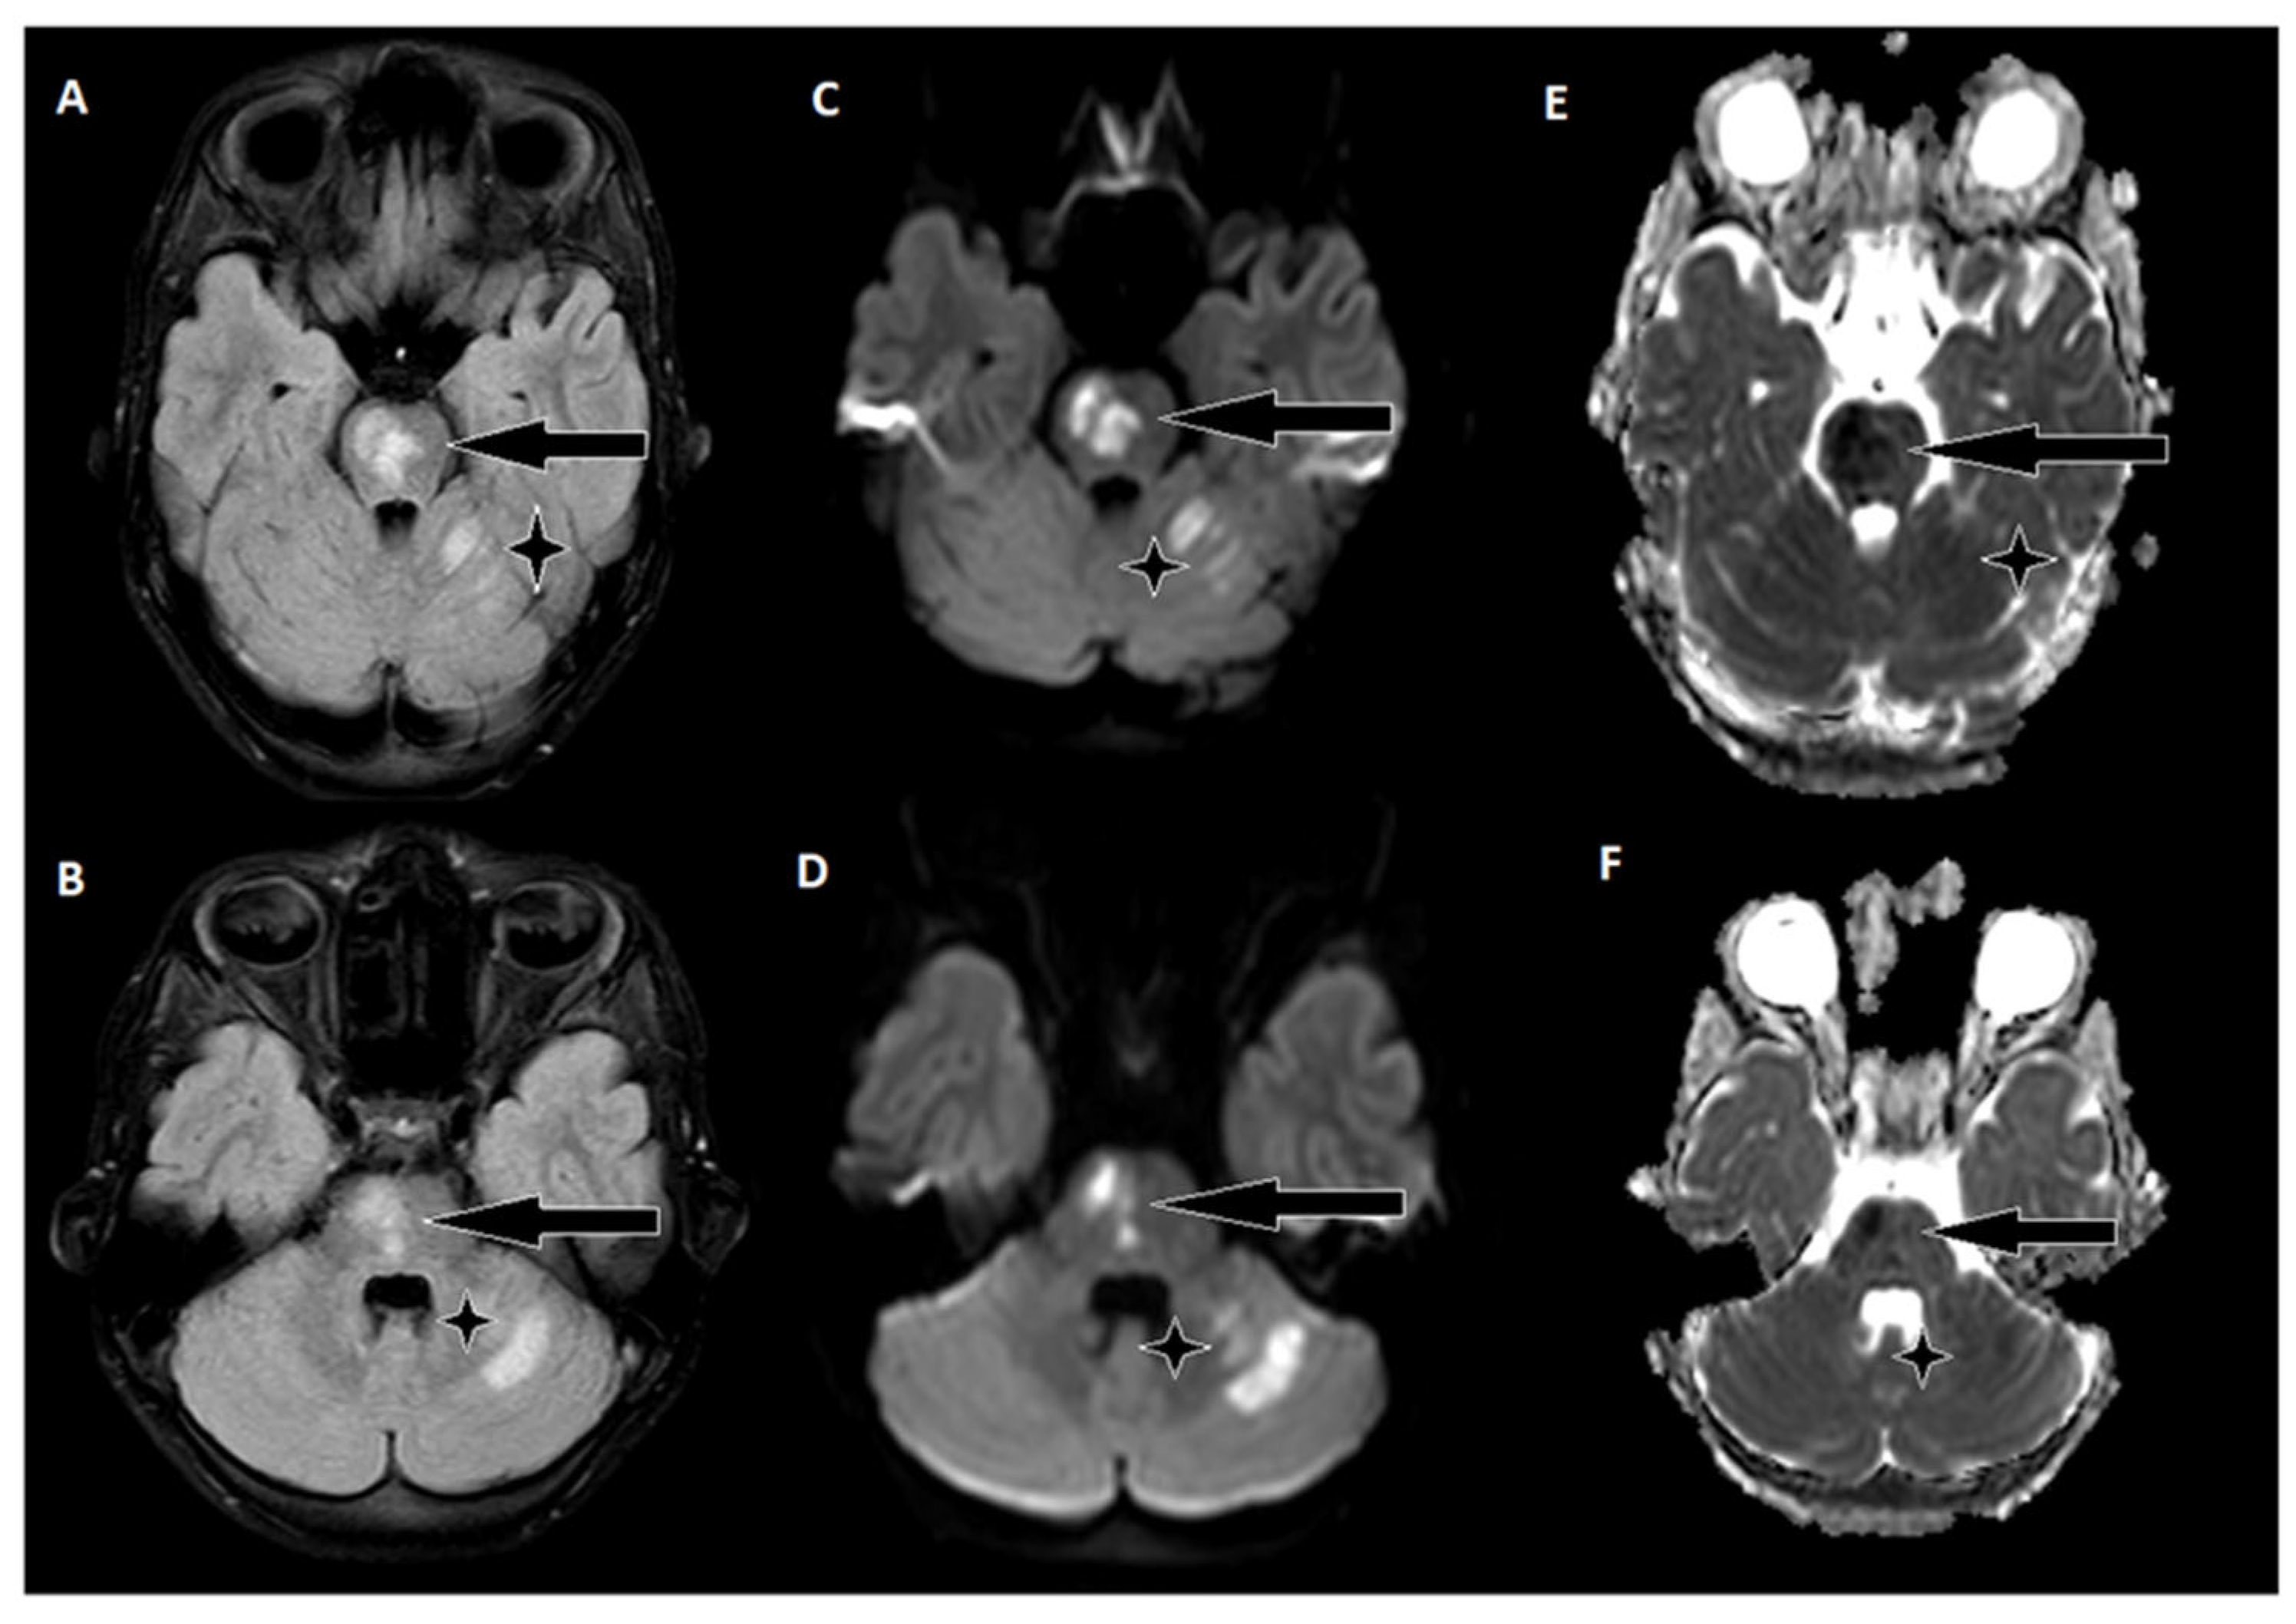

Figure 1. Emergency CT scan of the brain. (A) hypodense region in the left thalamic region; (B) hyperdense basilar artery (HDBA) sign; (C) 2 hypodense regions in the left cerebellum.

A 9-year-old male was admitted to a regional hospital due to a persistent complaint of diarrhea, exceeding ten episodes in two days, accompanied by a single episode of vomiting, tension headache, and mild vertigo. Initial diagnostic assessments did not reveal any notable abnormalities, leading to a diagnosis of gastroenteritis. Following rehydration therapy, the patient's overall condition improved, and discharge plans were being considered. However, on the subsequent day after admission, at approximately 16:00, the patient suddenly experienced weakness localized to the left side of his body. Recognizing the urgency of the situation, an emergency consultation with a neurologist was promptly arranged. Two hours following the onset of these new symptoms, a computed tomography (CT) scan of the brain was conducted, which did not show any acute changes in the brain. Nevertheless, the CT scan did reveal two hypodense regions in the left cerebellum, which raised suspicion of malignancy, along with a hyperdense appearance of the basilar artery (BA). Additionally, a hypodense region was noted in the left thalamic region, suggesting a potential prior lacunar stroke.